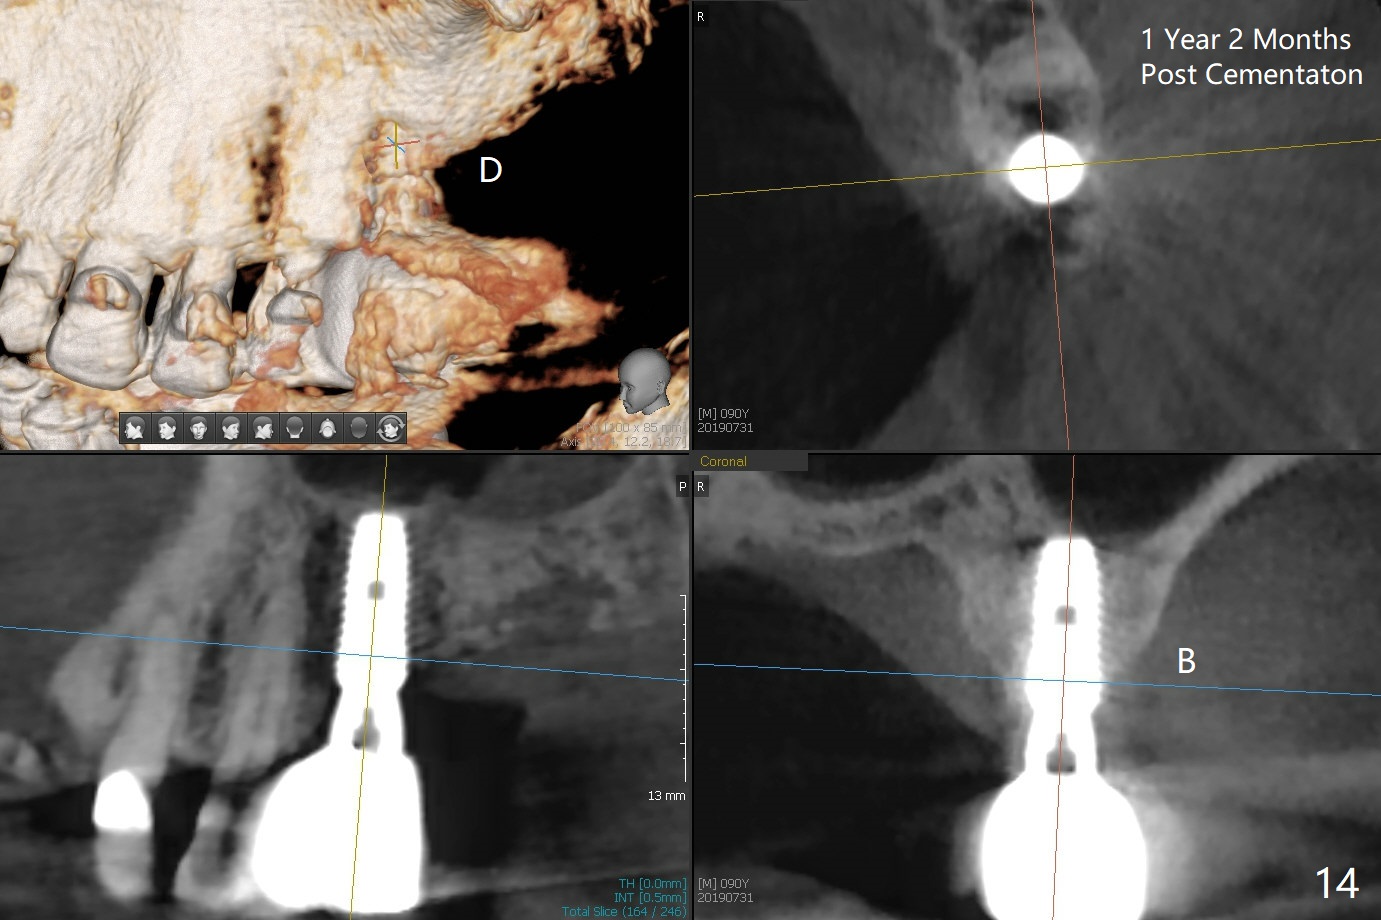

The septum is found to be pointed after extraction of the tooth #14 (Fig.1 *). The septum is flattened with Rongeur (Fig.2 *) prior to osteotomy. Because of interference of the mesial bone (Fig.3 *), osteotomy does not reach the depth with use of stopper. Without the latter, a 5x11.5 mm implant barely penetrates the sinus floor (Fig.4 (no postop nasal hemorrhage)). Also due to the mesial bone interference, a 6.5 mm abutment is not seated. Finally a 5.5x7(5) mm abutment is placed for an immediate provisional. Periodontal dressing is applied to cover the buccal repaired gingiva (Fig.5 *). There is minimal thread exposure after removal of the provisional nearly 2 months postop (Fig.6). The provisional does not return for easy self cleansing. In fact this is not an easy task, because of the posterior position (Fig.8 (after Piezo scaling)). The distal implant remains exposed; the abutment is removed and a healing screw is placed (Fig.9). The implant should have been subcrestal distally (Fig.7 <, nearly 3 months postop). One month later, the implant seems to be buried (Fig.10). The straight abutment is changed to an angled one (4.5 x15 degree A (5) mm) before impression retake (Fig.11,12 (<, dashed line: access hole)). The implant should have been placed more mesial (Fig.13). Surgical guide is needed. There is no implant exposure clinically or in CBCT sections 1 year 2 months post cementaton (Fig.14), although 3 D image suggests missing distopalatal plate (Fig.15).